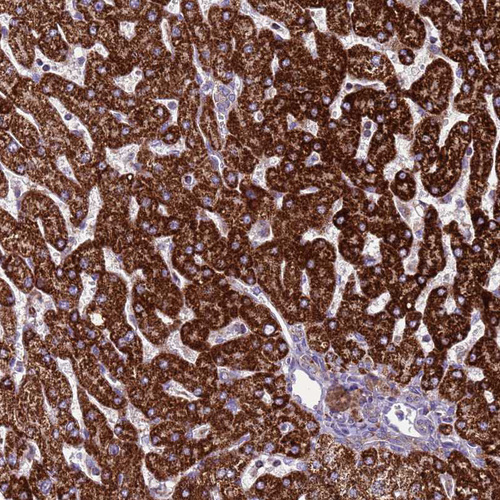

Immunohistochemistry analysis in human liver and testis tissues using HPA048492 antibody. Corresponding GCDH RNA-seq data are presented for the same tissues.